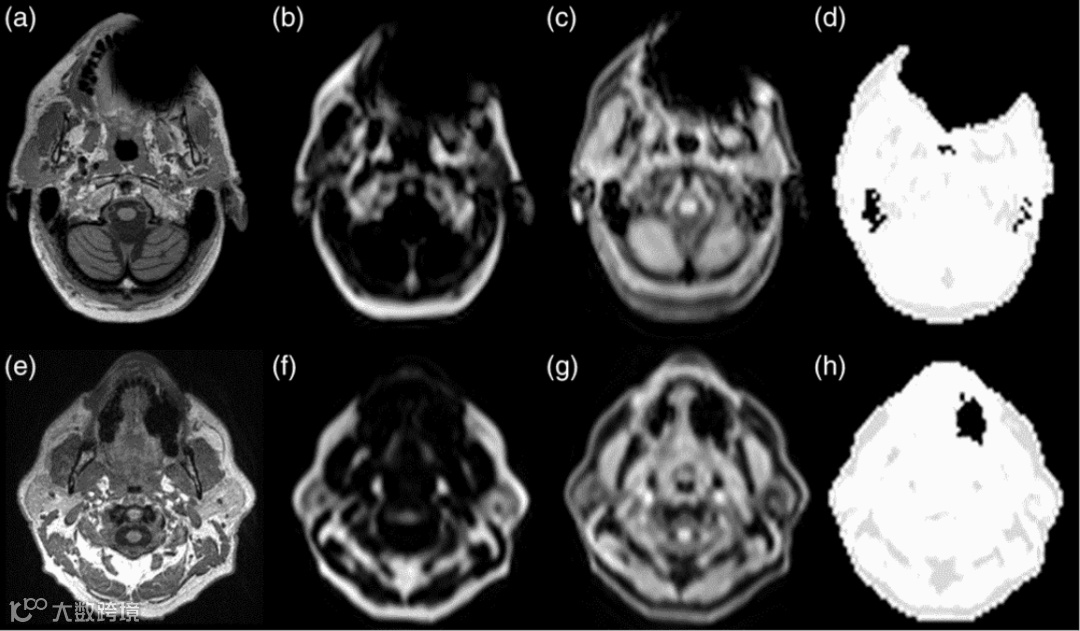

在检查过程中,MRI出现伪影会影响检查结果的准确判断。伪影包括运动伪影,金属伪影,化学位移伪影和卷褶伪影。运动伪影在MRI中比较常见,原因是患者的呼吸、心脏搏动或者咳嗽等原因导致的。在检查前,对患者做好心理疏导,缓解其紧张情绪可以减少运动伪影,另外也可使用补偿来调整。在MR诊断过程中,需要保持主磁场和梯度场的均匀和稳定,在受到铁磁性金属干扰时,会使主磁场受到影响形成伪影。受检者口腔内的金属假牙、或者其他体内留置金属器械等会造成不同程度的伪影,影响检测结果。

假牙产生的MRI伪影